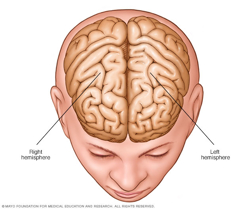

Brain hemispheres

The brain is divided into two halves, called hemispheres.

- Corpus callosotomy. This surgery completely or partially removes part of the brain that connects nerves on the right and left sides of the brain. This area is called the corpus callosum. This procedure is performed most often on children who experience irregular brain activity that spreads from one side of the brain to the other.

- Hemispherectomy. This procedure removes one side of the brain, called a hemisphere, which is part of the folded gray matter of the brain. The gray matter area is called the cerebral cortex. This surgery is usually performed only in children who have seizures that start in different areas within one brain hemisphere. These types of seizures usually result from a condition that is present at birth or in early infancy.

- Functional hemispherectomy. This procedure is mostly performed on children to remove the connecting nerves without removing actual pieces of the brain.